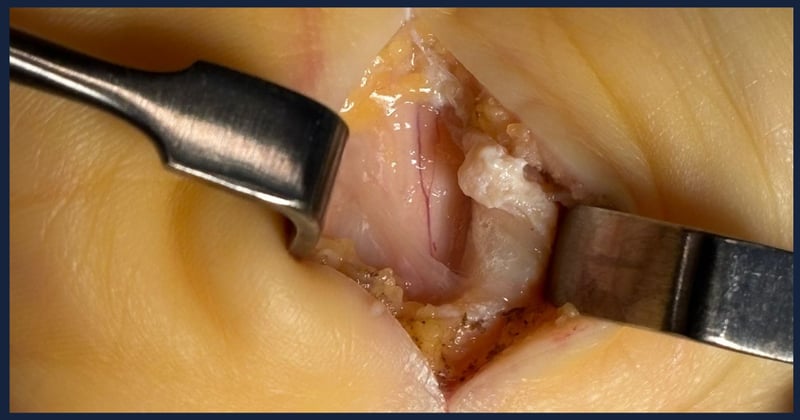

Artroscopia de muñecaArtroscopia de muñeca

+2+2